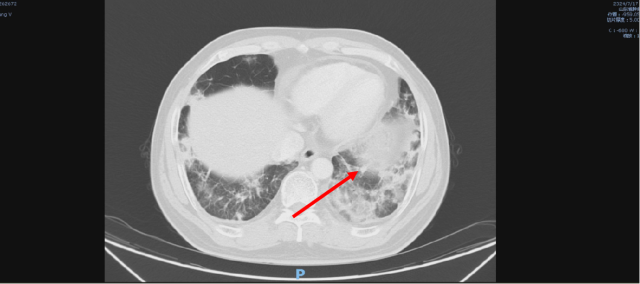

伏罗尼布+依维莫司治疗后,2024-07-17 复查 CT

2024-07-17 CT

伏罗尼布治疗后,2024-09-09 复查CT

1. 考虑双肺炎症改变,较前范围减小,建议复查

2. 双肺多发结节,较前减小。

3. 双肺多发纤维灶。

4. 心包积液。

5. 肝内多发低密度病变,结合病史,不除外转移瘤可能,较前部分减小:建议必要时 CT 增强扫描进一步检查。

6. 考虑:肝左叶囊肿。